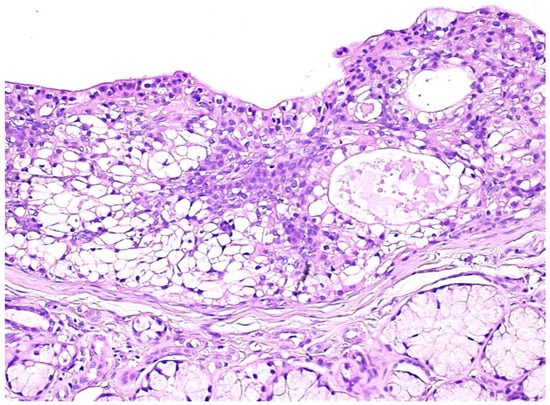

Gross examination disclosed well defined cystic lesions, and microscopically, at scanning magnification, a single cystic space was detectable in all samples, showing parietal proliferation of clusters of epithelial cells with a focal cribriform growth pattern (Figure 2). The central part of the cyst was filled with proteinaceous material and cholesterol crystals, while a distinct and complete rim of collagenous stroma separated the cyst from the surface epithelium and from adjacent lobules of mucous salivary glands. The clusters of epithelial proliferation (Figure 3) were composed by small columnar and intermediate cells, cells with prominent cytoplasmic clearing and marginated nuclei, scattered flat to polygonal cells showing epidermoid differentiation and a reduced number of large mucous-producing cells with multivacuolated cytoplasm. The latter were better highlighted with Alcian Blue (Figure 4) and Mucicarmine stains and also showed PAS-positivity, which was partly abolished after diastase treatment. Occasionally, smaller cystic spaces with cribriform appearance were evident within the neoplastic epithelial clusters, which were lined by cuboidal to columnar cells. Nuclear pleomorphism was minimal, as was mitotic activity (<1/10 high power fields), while inflammatory infiltration, necrosis and perineural invasion were undetectable; additionally, tumor-free margins (> 1 mm) were assessed in all cases. Patients had been followed-up for a minimum of five years (range: 62–120 mo.; median: 68 mo.) and had remained without evidence of disease up to January 2019.

Figure 3. The epithelial component consisted of small columnar and intermediate cells, cells with prominent cytoplasmic clearing, rare flat to polygonal cells showing epidermoid differentiation and a reduced number of large mucous-producing cells with multivacuolated cytoplasm. (H&E, x10).